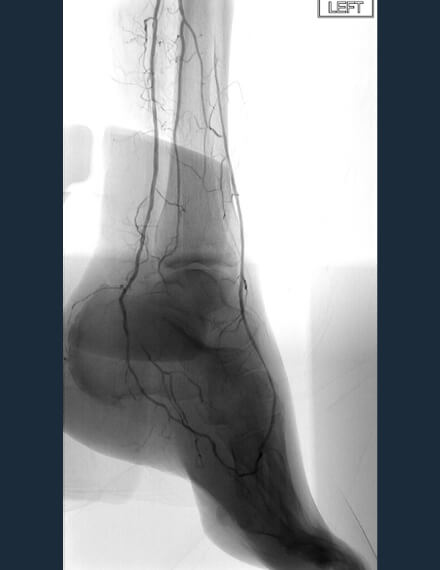

Pre-procedure

Baseline angio shows occluded lateral plantar and dorsalis pedis arteries. Ankle-brachial index (ABI) pre-procedure: 0.4. -

Final Treatment

After final treatment with 2.0 mm PTA balloon, final angio shows reconstitution of flow around the foot arch. ABI post-procedure: 0.8.